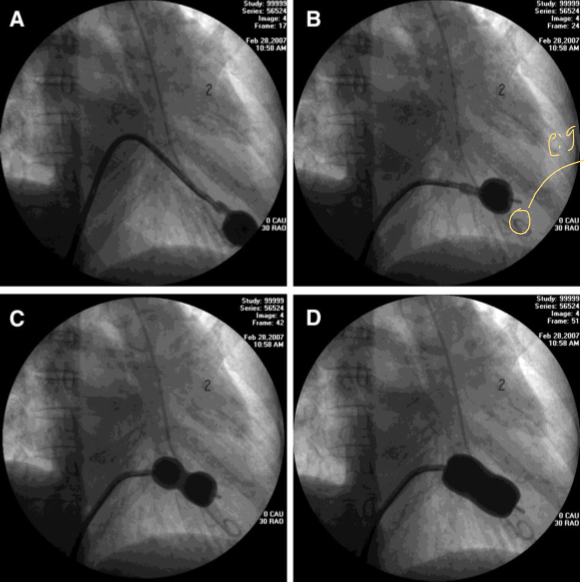

what is occurring here

Mitral Stenosis

what is occurring in this image

Balloon mitral valvuloplasty

MS

WHAT PROCEDURE IS HAPPENING

MITRAL VALVULOPLASTY

to treat mitral stenosis the **** balloon must go *****

Inoue balloon must go transseptal

an INOUE balloon is used to treat what

mitral valve stenosis